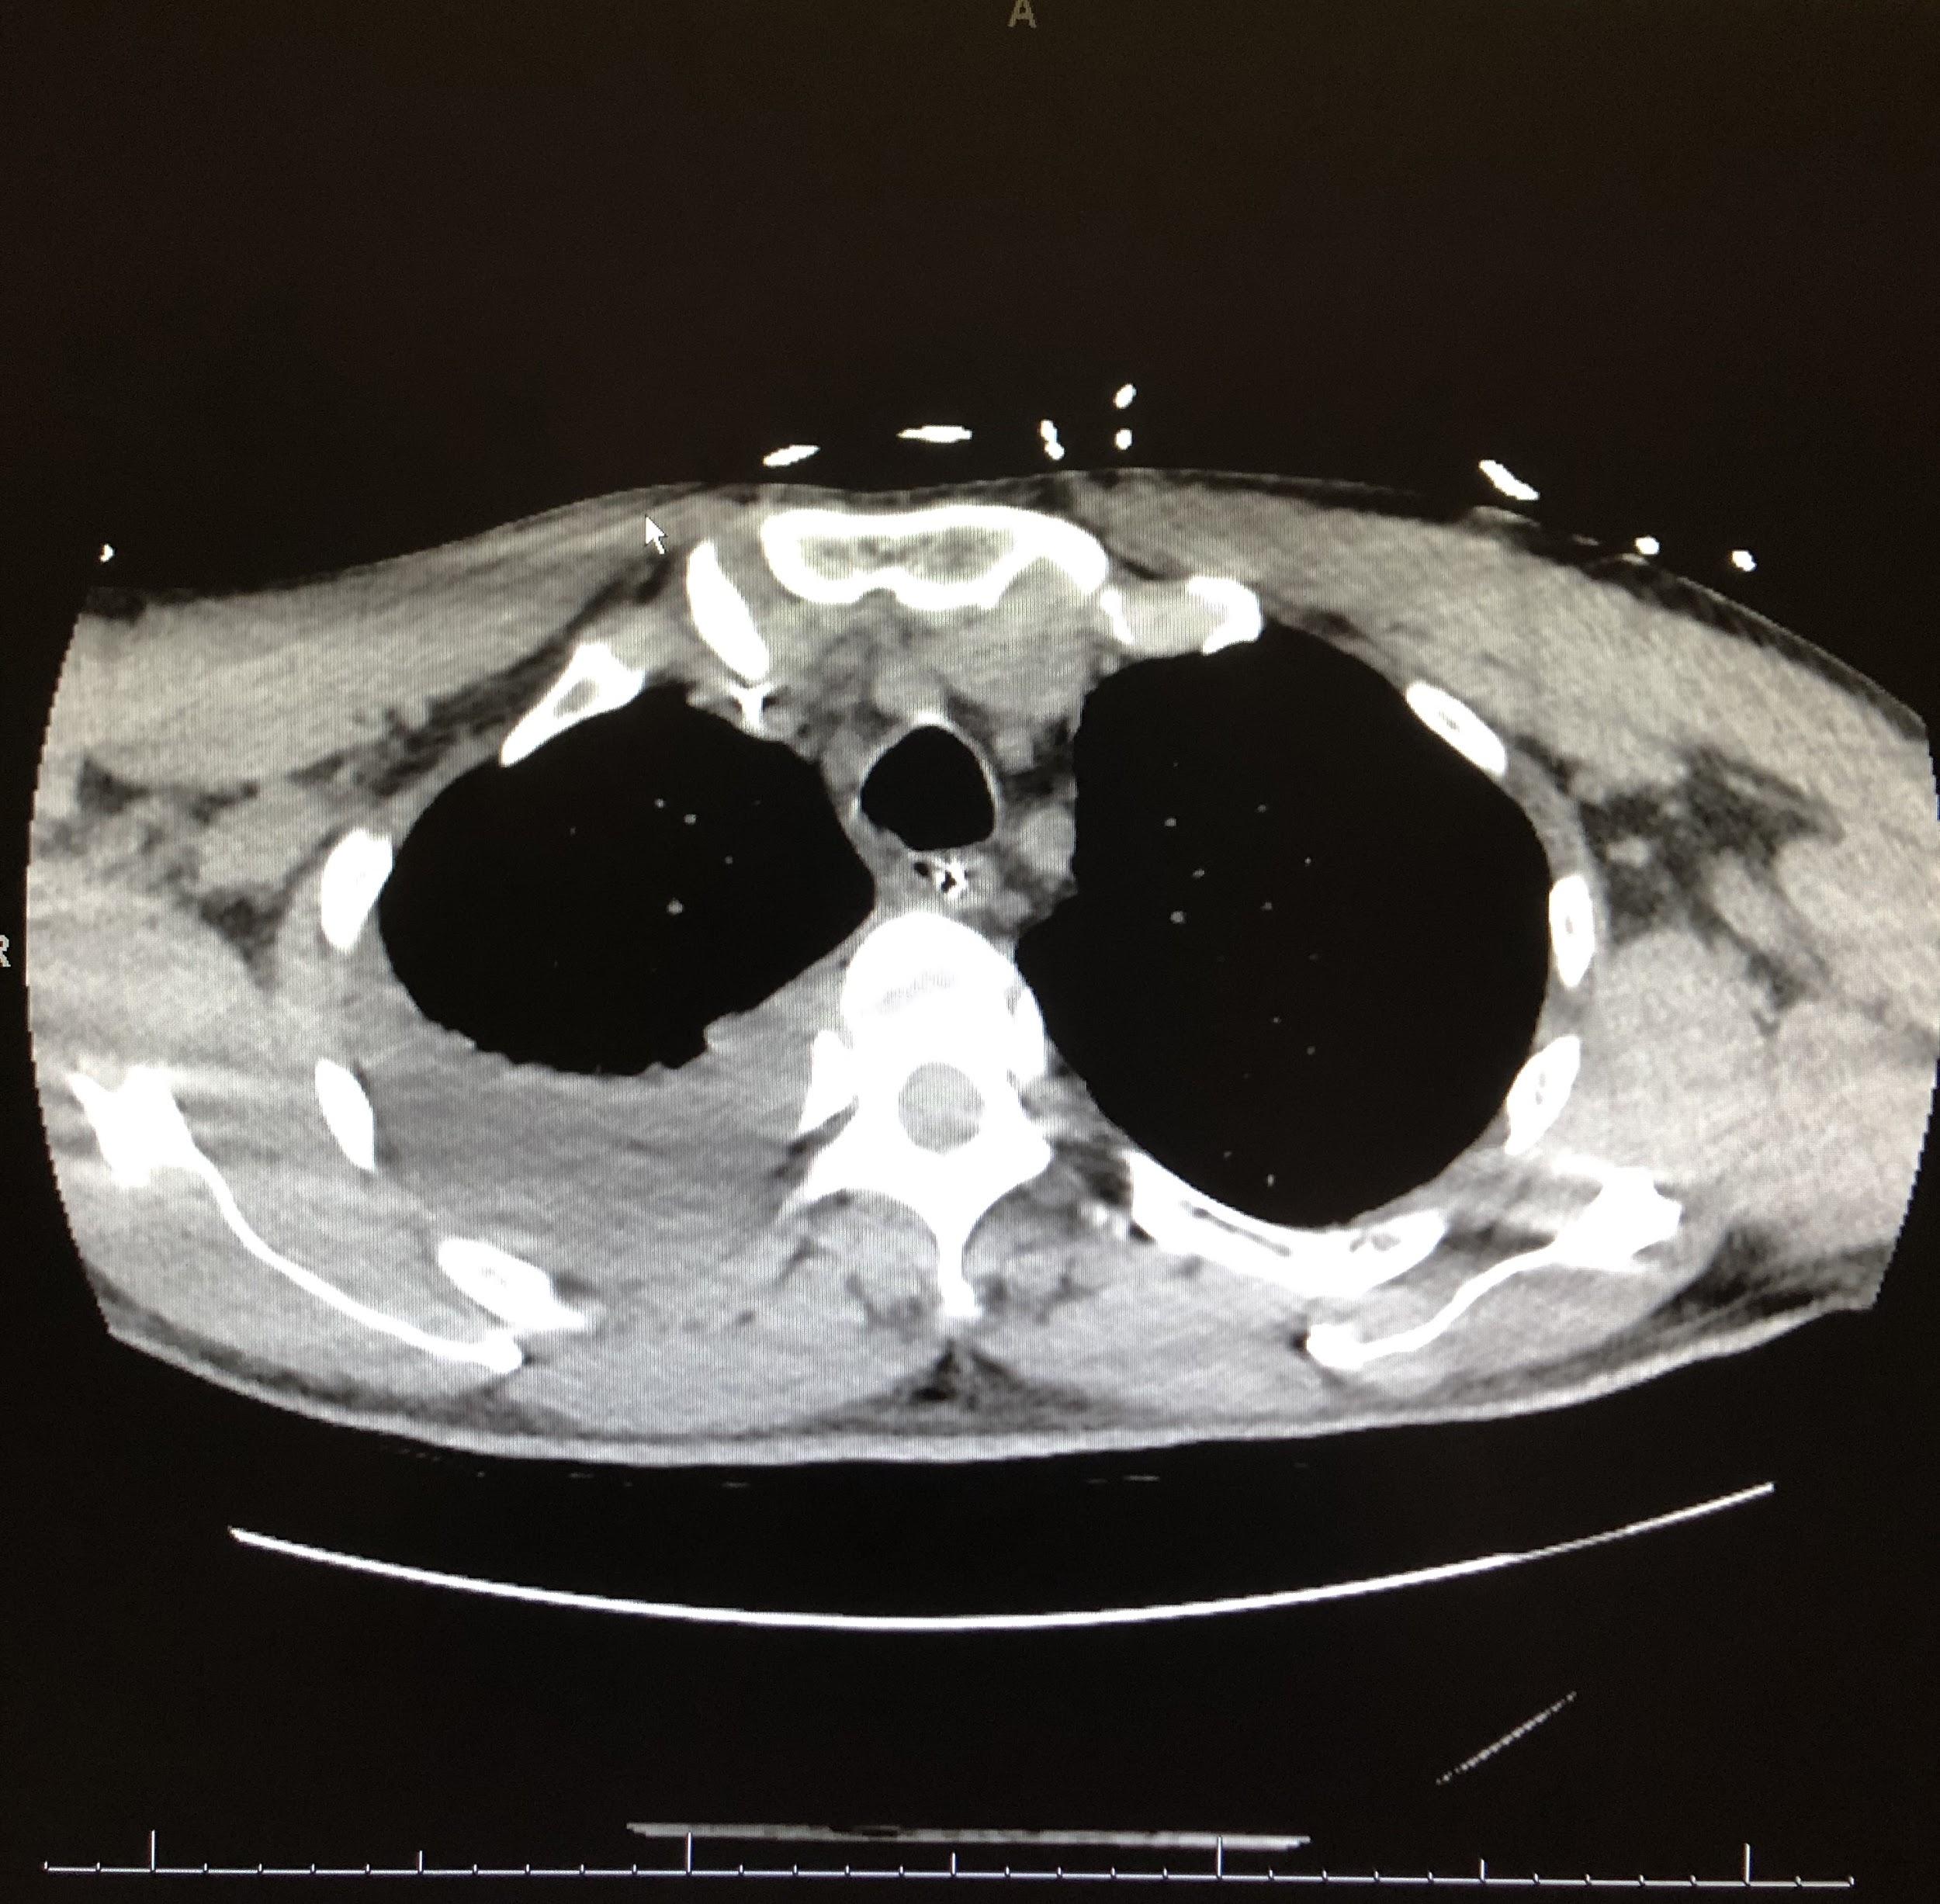

Computed tomography (CT) scans of the chest revealed continued right lower-lobe consolidation and a moderate right-sided pleural effusion (Figure 3). The patient subsequently underwent chest-tube placement, and his clinical status improved; following successful extubation, he was transferred out of the ICU.

Figure 3. CT scans of chest demonstrated a focal area of consolidation in the right middle and lower lobes (top) and moderate right-sided pleural effusion (bottom).